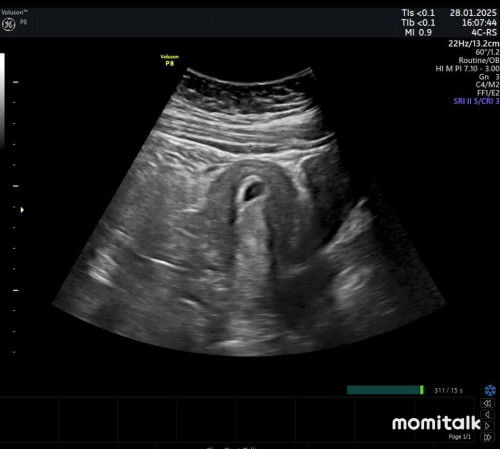

Hamil 6 week 2 days, flek darah tanggal 6 feb 24, udah usg kantong aman mmg ada pendarahan karna kontraksi awal, sudah di reseptin microgest 100 mg, kantung membesar normal tapi belum ada janin, ada yg punya cerita serupa mau sharing saja skrng masih flek tapi warna coklat bukan merah darah lagi

Mau cerita mungkin bisa cari bahan diskusi, haid terkahir 3 des 24 sempet tespek dulu ternyata negatif karna waktu itu demam mau periksa, terus 2 januari 25 tespek ternyata garis 2 menurut HPL tgl 8 sep 25, nah kmrin usg harusnya pas 8 week menurut hitungan hpht tapi menurut diameter kantong rahim 0,7 itu masih usia 5-6 week, disuruh balik lagi 2 minggu, haidku mmg tidak teratur selama ini, bisa maju mundur tapi 1 bulan pasti haid, apa mmg kesuburan beda” ditentukan masa haidnya dan HPL mmg hanya perkiraan saja, karna kesuburanku seperti itu bisa jdi perhitungan HPL juga bisa salah ? Apa ada yg punya kasus serupa, agak ovt karna hamil pertama